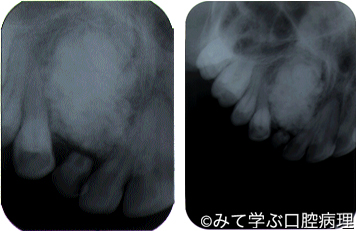

複雑性歯牙腫

上顎犬歯相当部の顎骨内に不透過像を認める

上顎乳犬歯が晩期残存している

上顎側切歯と第一小臼歯に歯軸の傾斜を認める